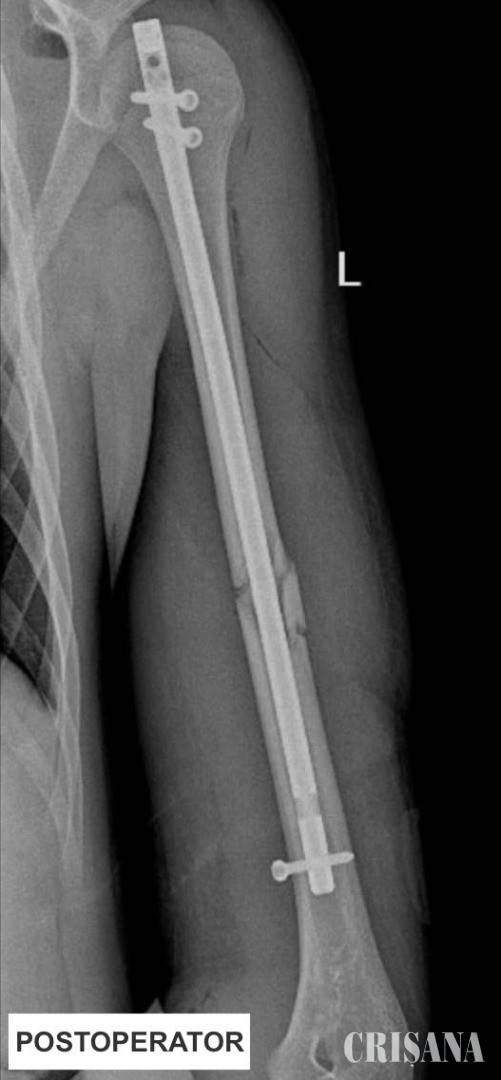

Primul pas a presupus repunerea la loc a celor două fragmente ale osului fracturat. Cu ajutorul unor truse speciale și a ghidajului radiologic, chirurgii au introdus tija pentru a asigura poziția osului fracturat. Acest abord a presupus efectuarea de radiografii repetate în timpul intervenției pentru a se vedea unde este tija și cât de aproape este de focarul de fractură. După poziționarea acesteia pe os, următorul pas a fost montarea a 3 șuruburi pentru ancorarea tijei în humerus. Tija de titan este de calibrul canalului medular, având dimensiuni de 28 cm lungime 8 phi în diametru. Intervenția a fost una de complexitate ridicată, humerusul fiind un os foarte greu de redus. Operația a avut loc în data de 20 aprilie, a durat o oră și jumătate și a decurs bine.

În momentul de față, starea adolescentului este foarte bună, acesta fiind deja externat. Datorită tehnicii operatorii, nu a mai fost necesar ca brațul să fie imobilizat cu gips, iar evoluția pacientului este favorabilă. Acesta a putut deja să își reia activitatea obișnuită de de zi cu zi, inclusiv să meargă la școală. Peste șase luni, pacientul va trebui să revină pentru scoaterea tijei.

Comparativ cu alte variante de tratament chirurgical, această tehnică operatorie presupune o serie de avantaje pentru pacient, precum: timp operator redus, minimizarea complicațiilor intraoperatorii, respectiv postoperatorii și recuperarea mai rapidă a pacientului, nefiind nevoie de gipsarea brațului. Abordul este minim invaziv, toate cele trei incizii având dimensiunea de maxim 3 centimetri.